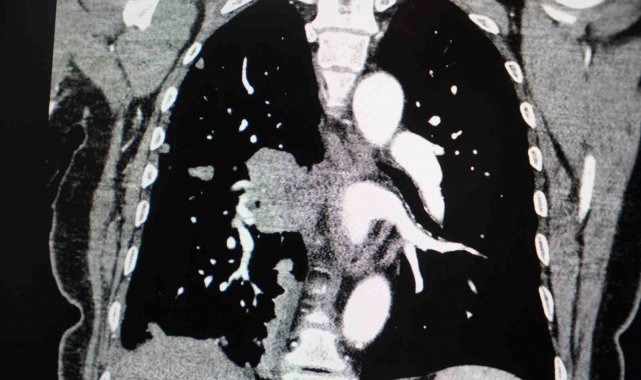

Akciğer kanseri vakalarındaki artışa da dikkat çeken Özkaya, "Son yıllarda hem sigara içen hem de hiç sigara kullanmamış bireylerde akciğer kanseri vakalarında dikkat çekici bir artış görüyoruz. Özellikle kadınlarda adenokarsinom tipi akciğer kanseri belirgin şekilde artış göstermektedir., Yapılan son araştırmalara göre akciğer kanseri teşhislerinin yaklaşık yüzde 20'si hiç sigara içmemiş bireylerde konuluyor. Bunun en önemli nedeni pasif içiciliktir. Yani siz sigara içmeseniz bile, yakın çevrenizde sigara içiliyorsa akciğer kanseri riskiyle karşı karşıya kalabilirsiniz" ifadelerini kullandı.